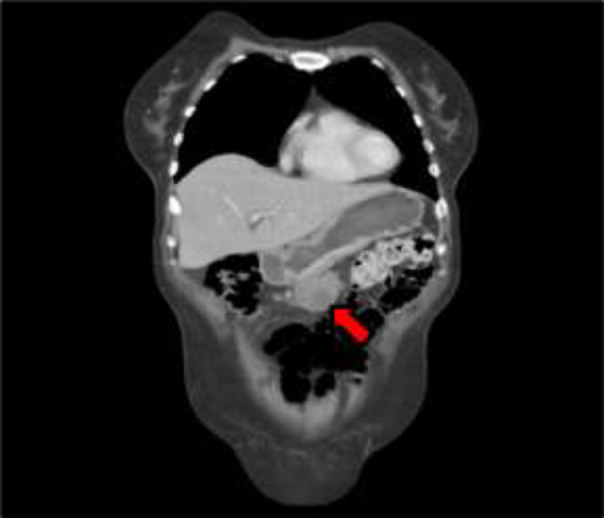

Case presentation: A 51-year-old woman presented with severe headache, vomiting, dizziness, blurred vision, tinnitus, bradyphrenia, reduced verbal fluency, sixth cranial nerve paresis, and non-reactive anisocoric pupils. Pleocytosis was found, with positive cytology for metastatic adenocarcinoma in cerebrospinal fluid, and a solid gastric mass defined as poorly differentiated adenocarcinoma. Due to her condition, the patient did not receive oncological management, evolving unfavorably and passing away twenty days later. Leptomeningeal carcinomatosis should be considered in patients with advanced cancer and meningeal symptoms. It is more predominant in women, with an average age of 53.84 years. Clinical presentation of leptomeningeal carcinomatosis varies, and diagnosis involves neuroimaging and cerebrospinal fluid cytology. Prognosis is unfavorable, often leading to fatality. Treatment protocols lack standardization, and personalized approaches, including targeted and systemic therapies, are explored for improved outcomes. The exceptional aspect of our case lies in the unique diagnosis of an abdominal tumor following the manifestation of neurological symptoms.

Abstract Image